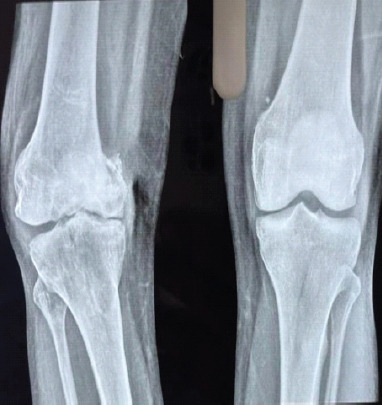

Case report: A case of a 38-year-old male who reported chronic right knee pain, swelling, and difficulty in ambulation due to a non-union Hoffa's fracture. Radiological findings indicated joint surface degeneration and instability. Given the chronicity and extent of articular damage, the patient underwent total knee arthroplasty (TKA) along with open reduction and internal fixation (ORIF) of the medial femoral condyle under spinal anesthesia. A posterior-stabilized knee system (Smith and Nephew, femur-5, tibia-5, polyethylene insert 13 mm) was implanted using Palacos bone cement. The patient recovered well and regained mobility with significant pain relief.